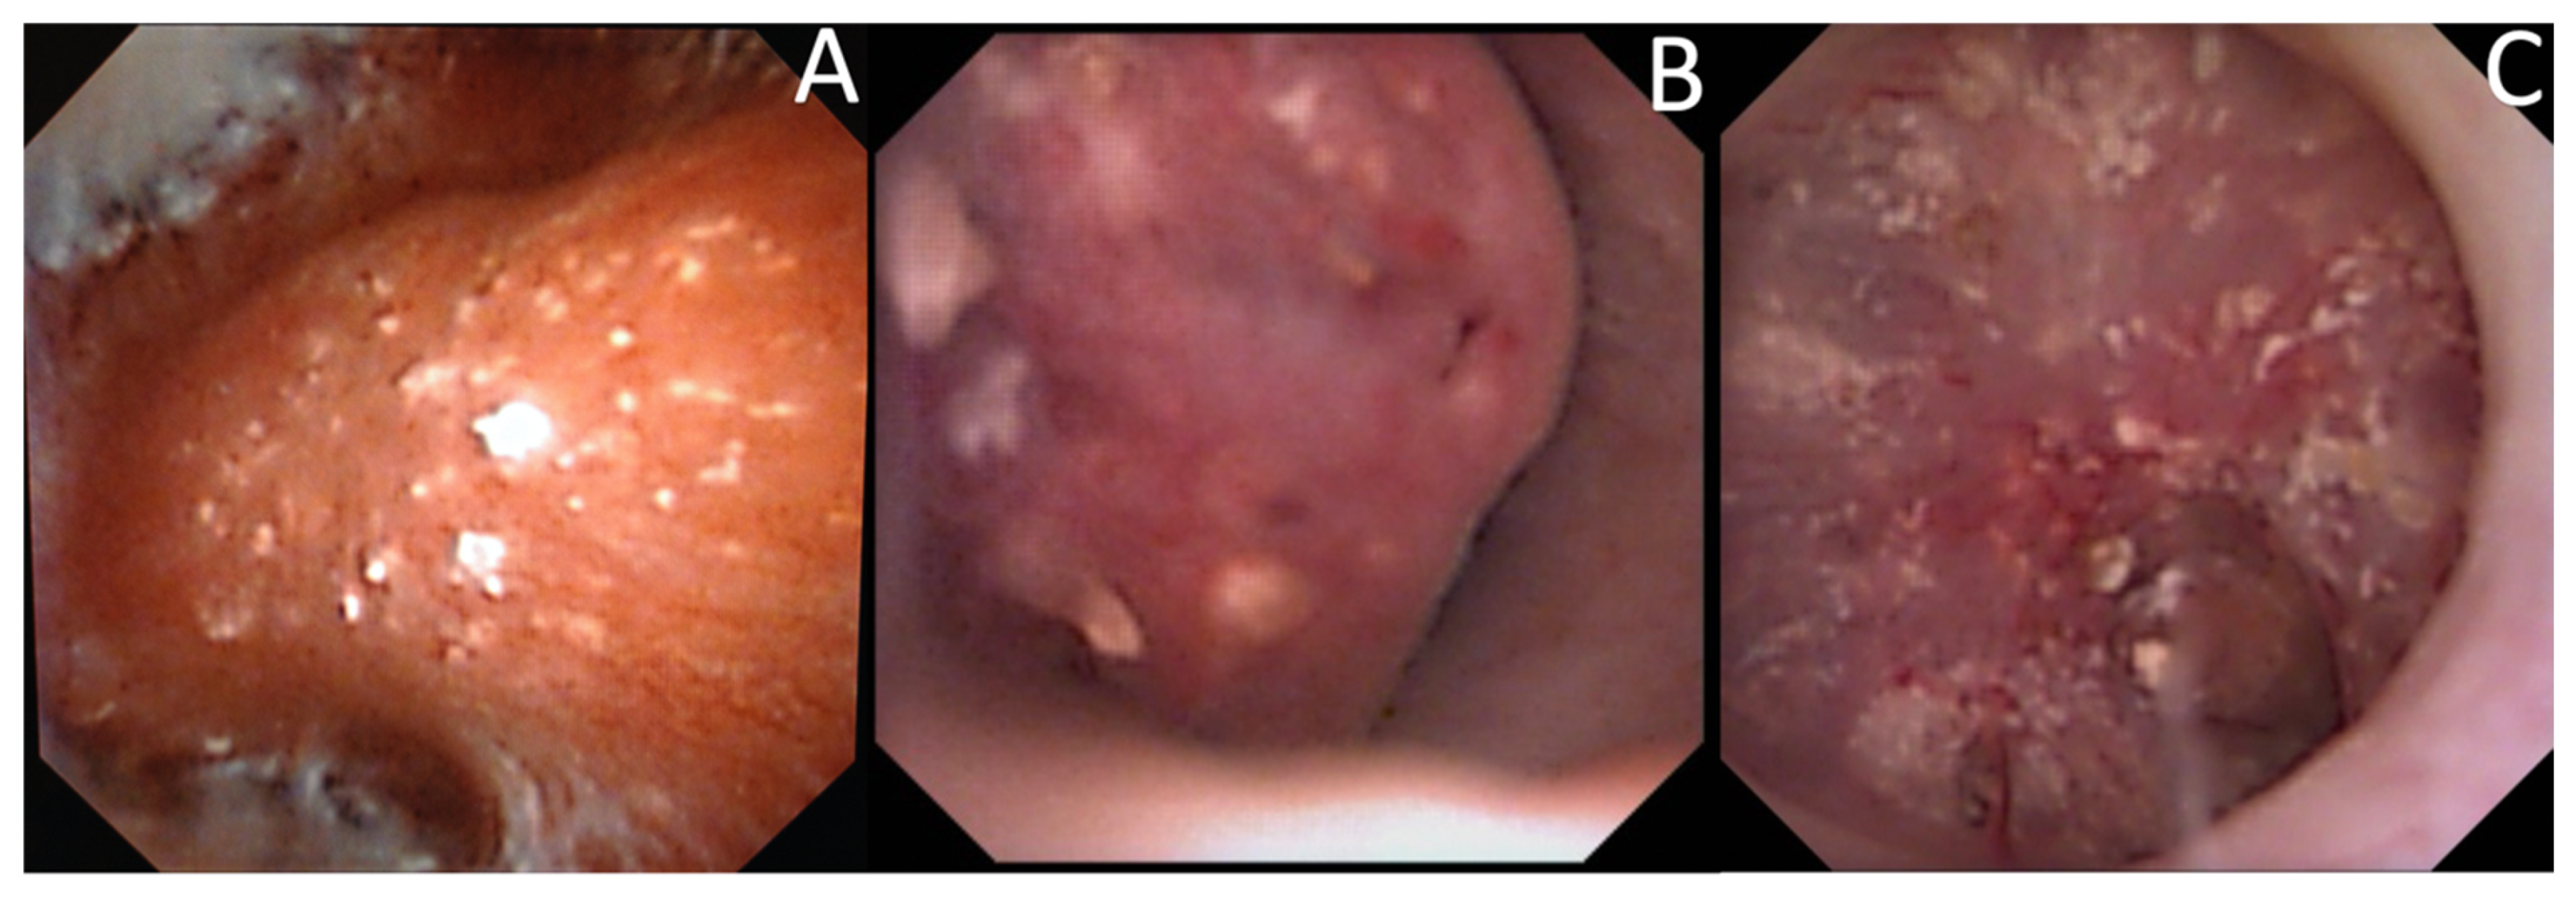

The description of intrapapillary or intraductal crystallization (Bellini plug origin) (Figure 4) was less common (15.9%) but was correlated with calcium phosphate stones (especially IVa2) and with a higher incidence of hypocitraturia (55.6%) and hypercalciuria (33%) [25]. Intraductal crystallization was related with different etiologies such as distal tubular acidosis [5] with the threat of impaired kidney function secondary to interstitial fibrosis that surrounds the Bellini ducts [17].

Figure 4.

Endoscopic aspects of intratubular crystallization. Their aspect is based on very thin, small, and well-delineated deposits. (A) Intraductal Bellini plugs, located in the central part of the papilla. (B) Intraductal crystallization, with the presence of small stones in the Bellini ducts. (C) Intraductal crystallization and intense peripheric intraductal plugging (that may begin in the loop of Henle), with the development of nephrocalcinosis.